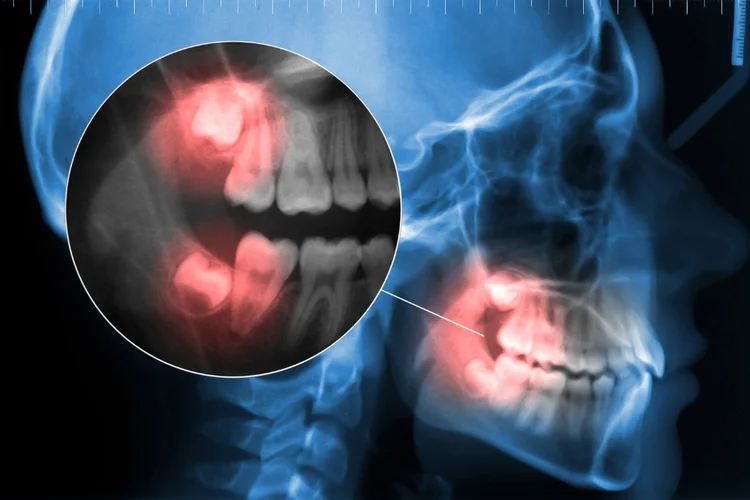

Even if symptoms are mild, it is advisable to have a dental evaluation to assess the

position and development of your wisdom teeth. This is typically done through a

clinical examination and dental imaging, such as X-rays.